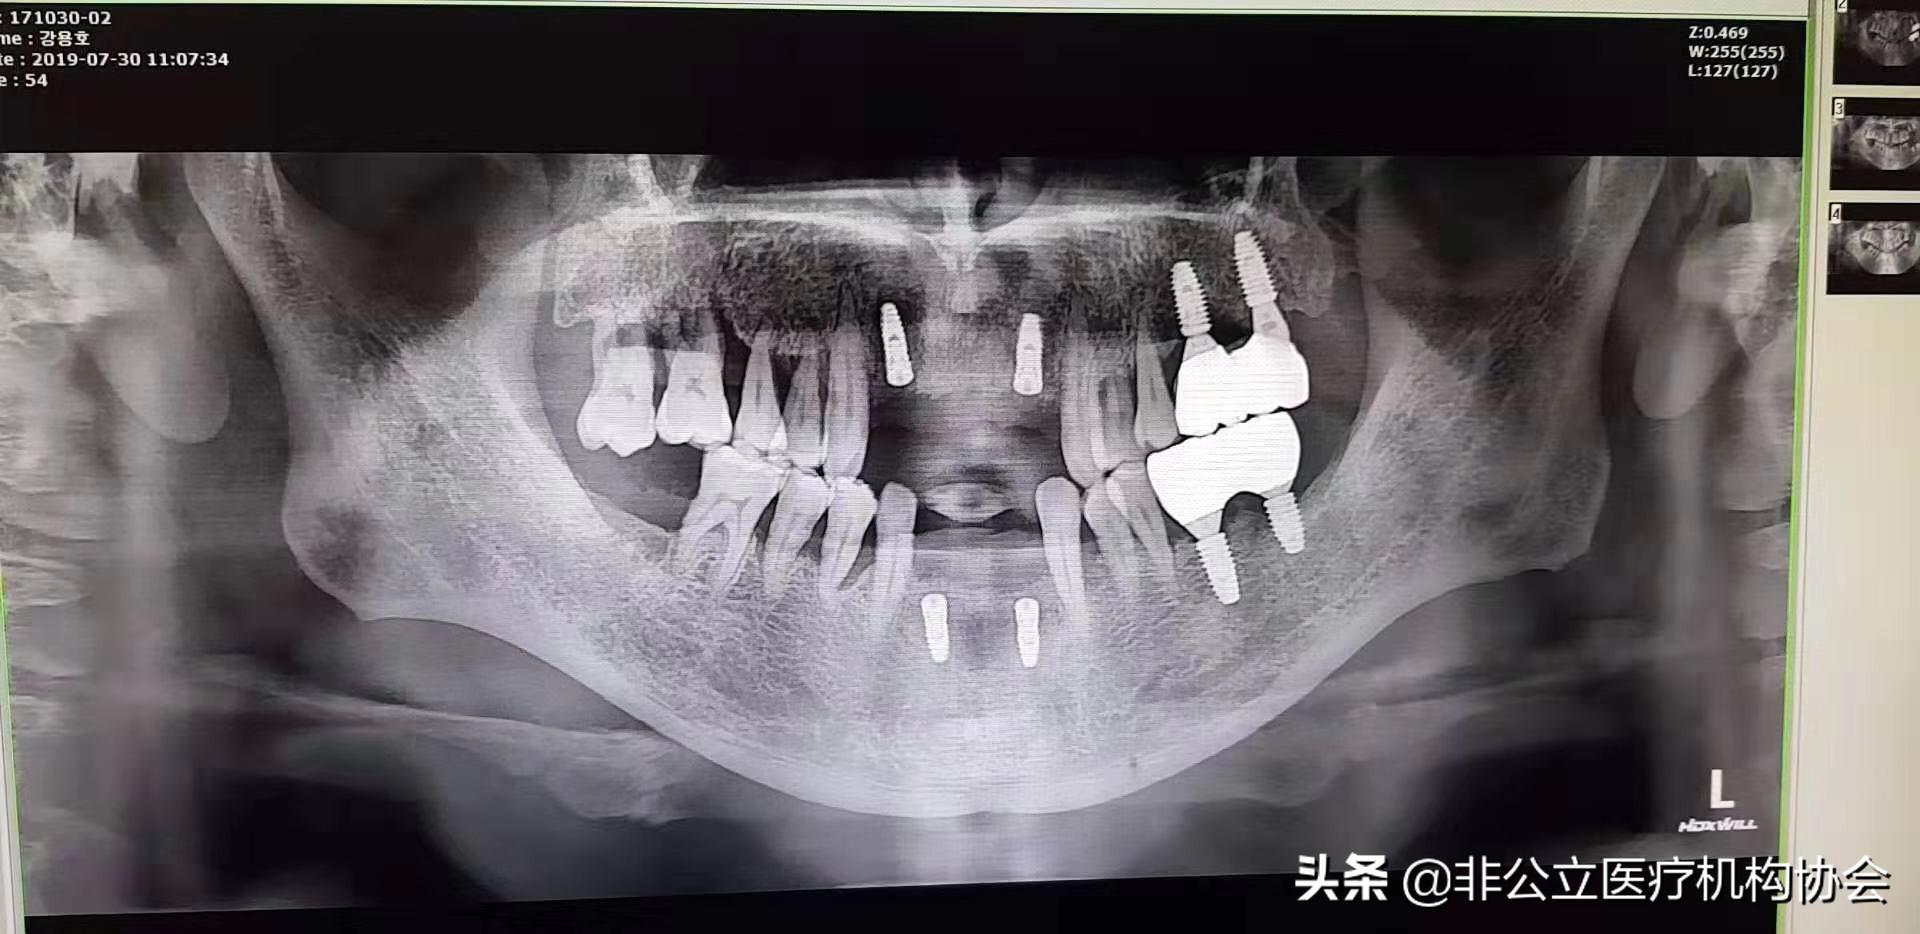

54歲患者術(shù)后X光照片

患者第二天來診所復(fù)診,上下頜恢復(fù)好,有一點輕微腫。

此病例第題部分修復(fù)完畢,一般經(jīng)過3~6個月的愈合時間,骨與種植體結(jié)合,義齒便可修復(fù)在種植體上制作完成了。